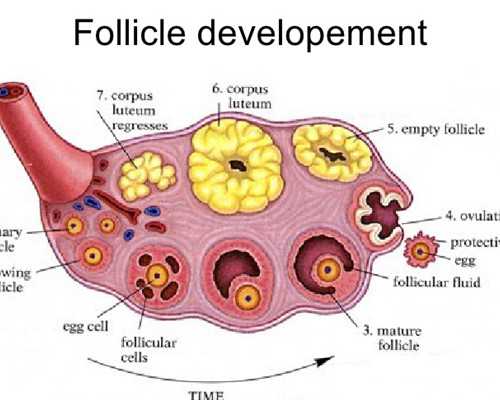

捐卵試管技術(shù):一代捐卵、二代捐卵

卵源等待時(shí)間:該院區(qū)卵源等待時(shí)間至少一年半起

2023煙臺(tái)市可開(kāi)展捐卵試管嬰兒技術(shù)的醫(yī)院共有2家,且均可開(kāi)展一代捐卵和二代捐卵試管技術(shù),不孕患者是可以將這2家醫(yī)院納入考慮范圍的。